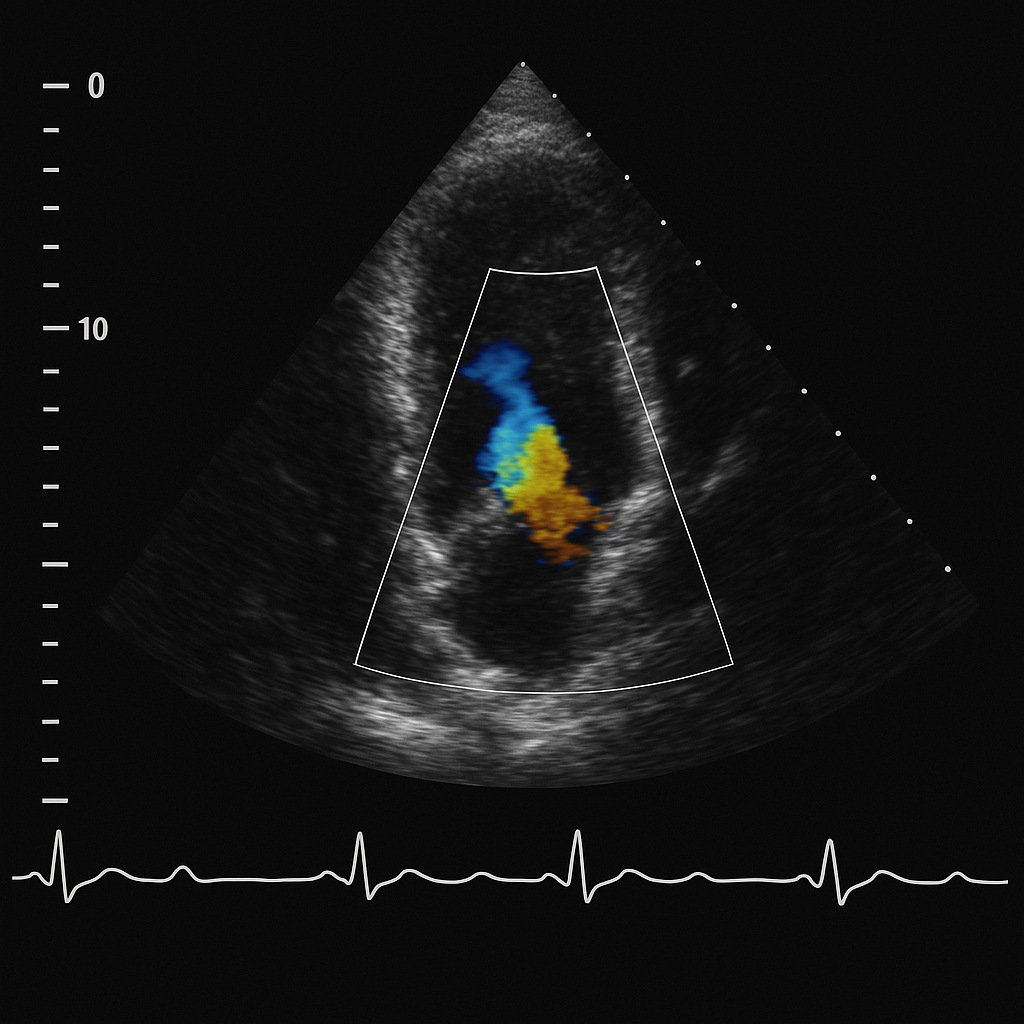

Ecocardiogramma

Ecografia del cuore per valutare la funzione cardiaca.